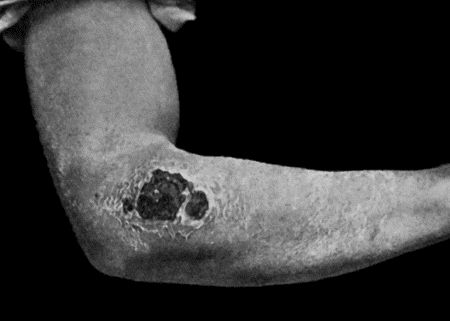

56.Sarcoma of Arm fungating 199

57.Carcinoma of Breast 206